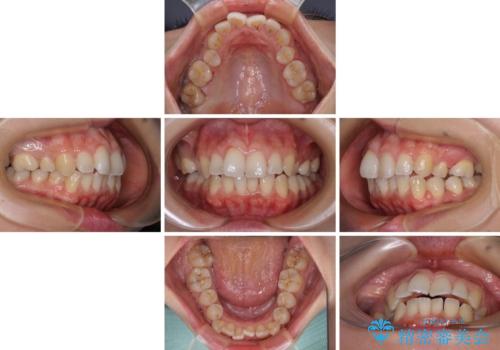

前歯のデコボコを改善 インビザラインの矯正治療

- 前歯のデコボコを治したいとのことで来院された患者様です。

上下顎ともに歯列全体の後方移動とIPR(歯と歯の間を削る)によってデコボコが解消するように設計し、インビザラインにより治療を行うこととしました。